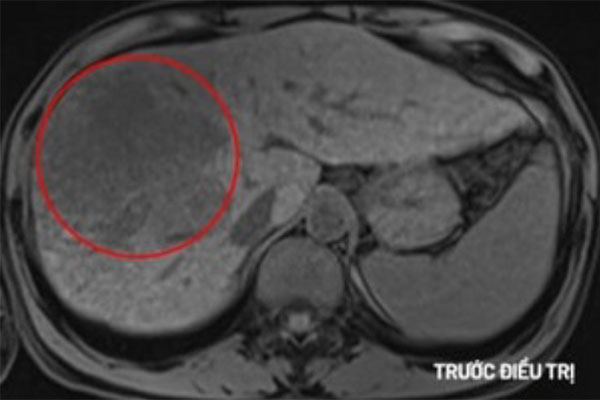

Xét nghiệm AFP cao bất thường nên các bác sĩ làm xét nghiệm chuyên sâu. Kết quả chụp MRI cho thấy khối u lớn ở gan phải với kích thước 10x10x12cm. Bác sĩ chẩn đoán anh C. mắc ung thư gan giai đoạn muộn.

Hình ảnh khối u gan của nam bệnh nhân. Ảnh: BVCC.